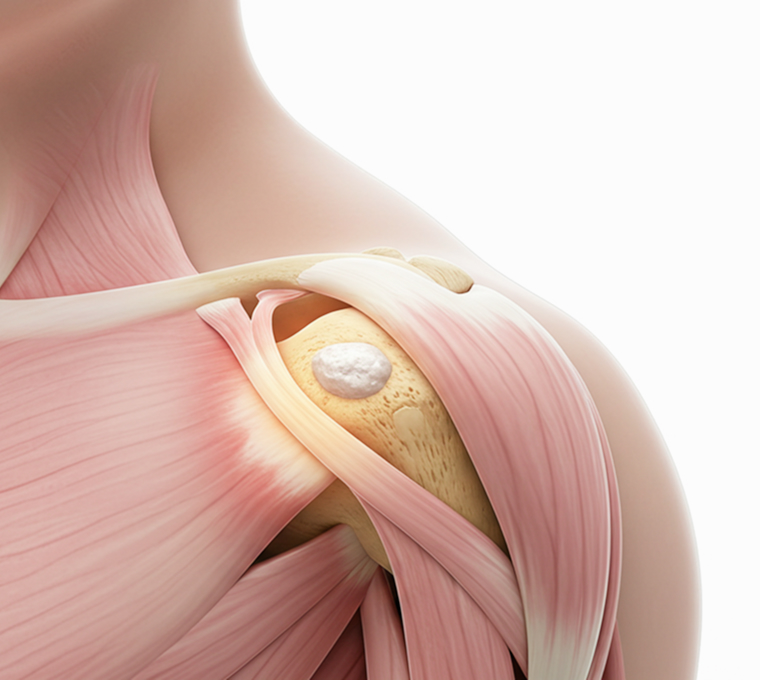

계단 오르기조차 힘든 무릎,

나이 탓만 하지 마세요!

무릎, 관절 손상의 원인을 분석해

연골 보호와 염증 반응을 개선할 수 있습니다.